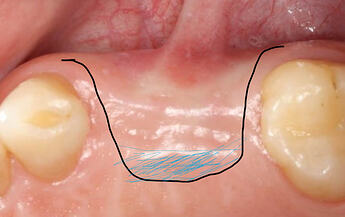

not sure if I can still reply this post, just wonder have you considered using S rolled flap with de-epithelialization to uncover implants instead of using palatal pedicle CTG? just like the attached picture, as shown below, blue area is the area of de-epitheliazation before tug around implant healing abutment. like Richard kern’s lecture ?